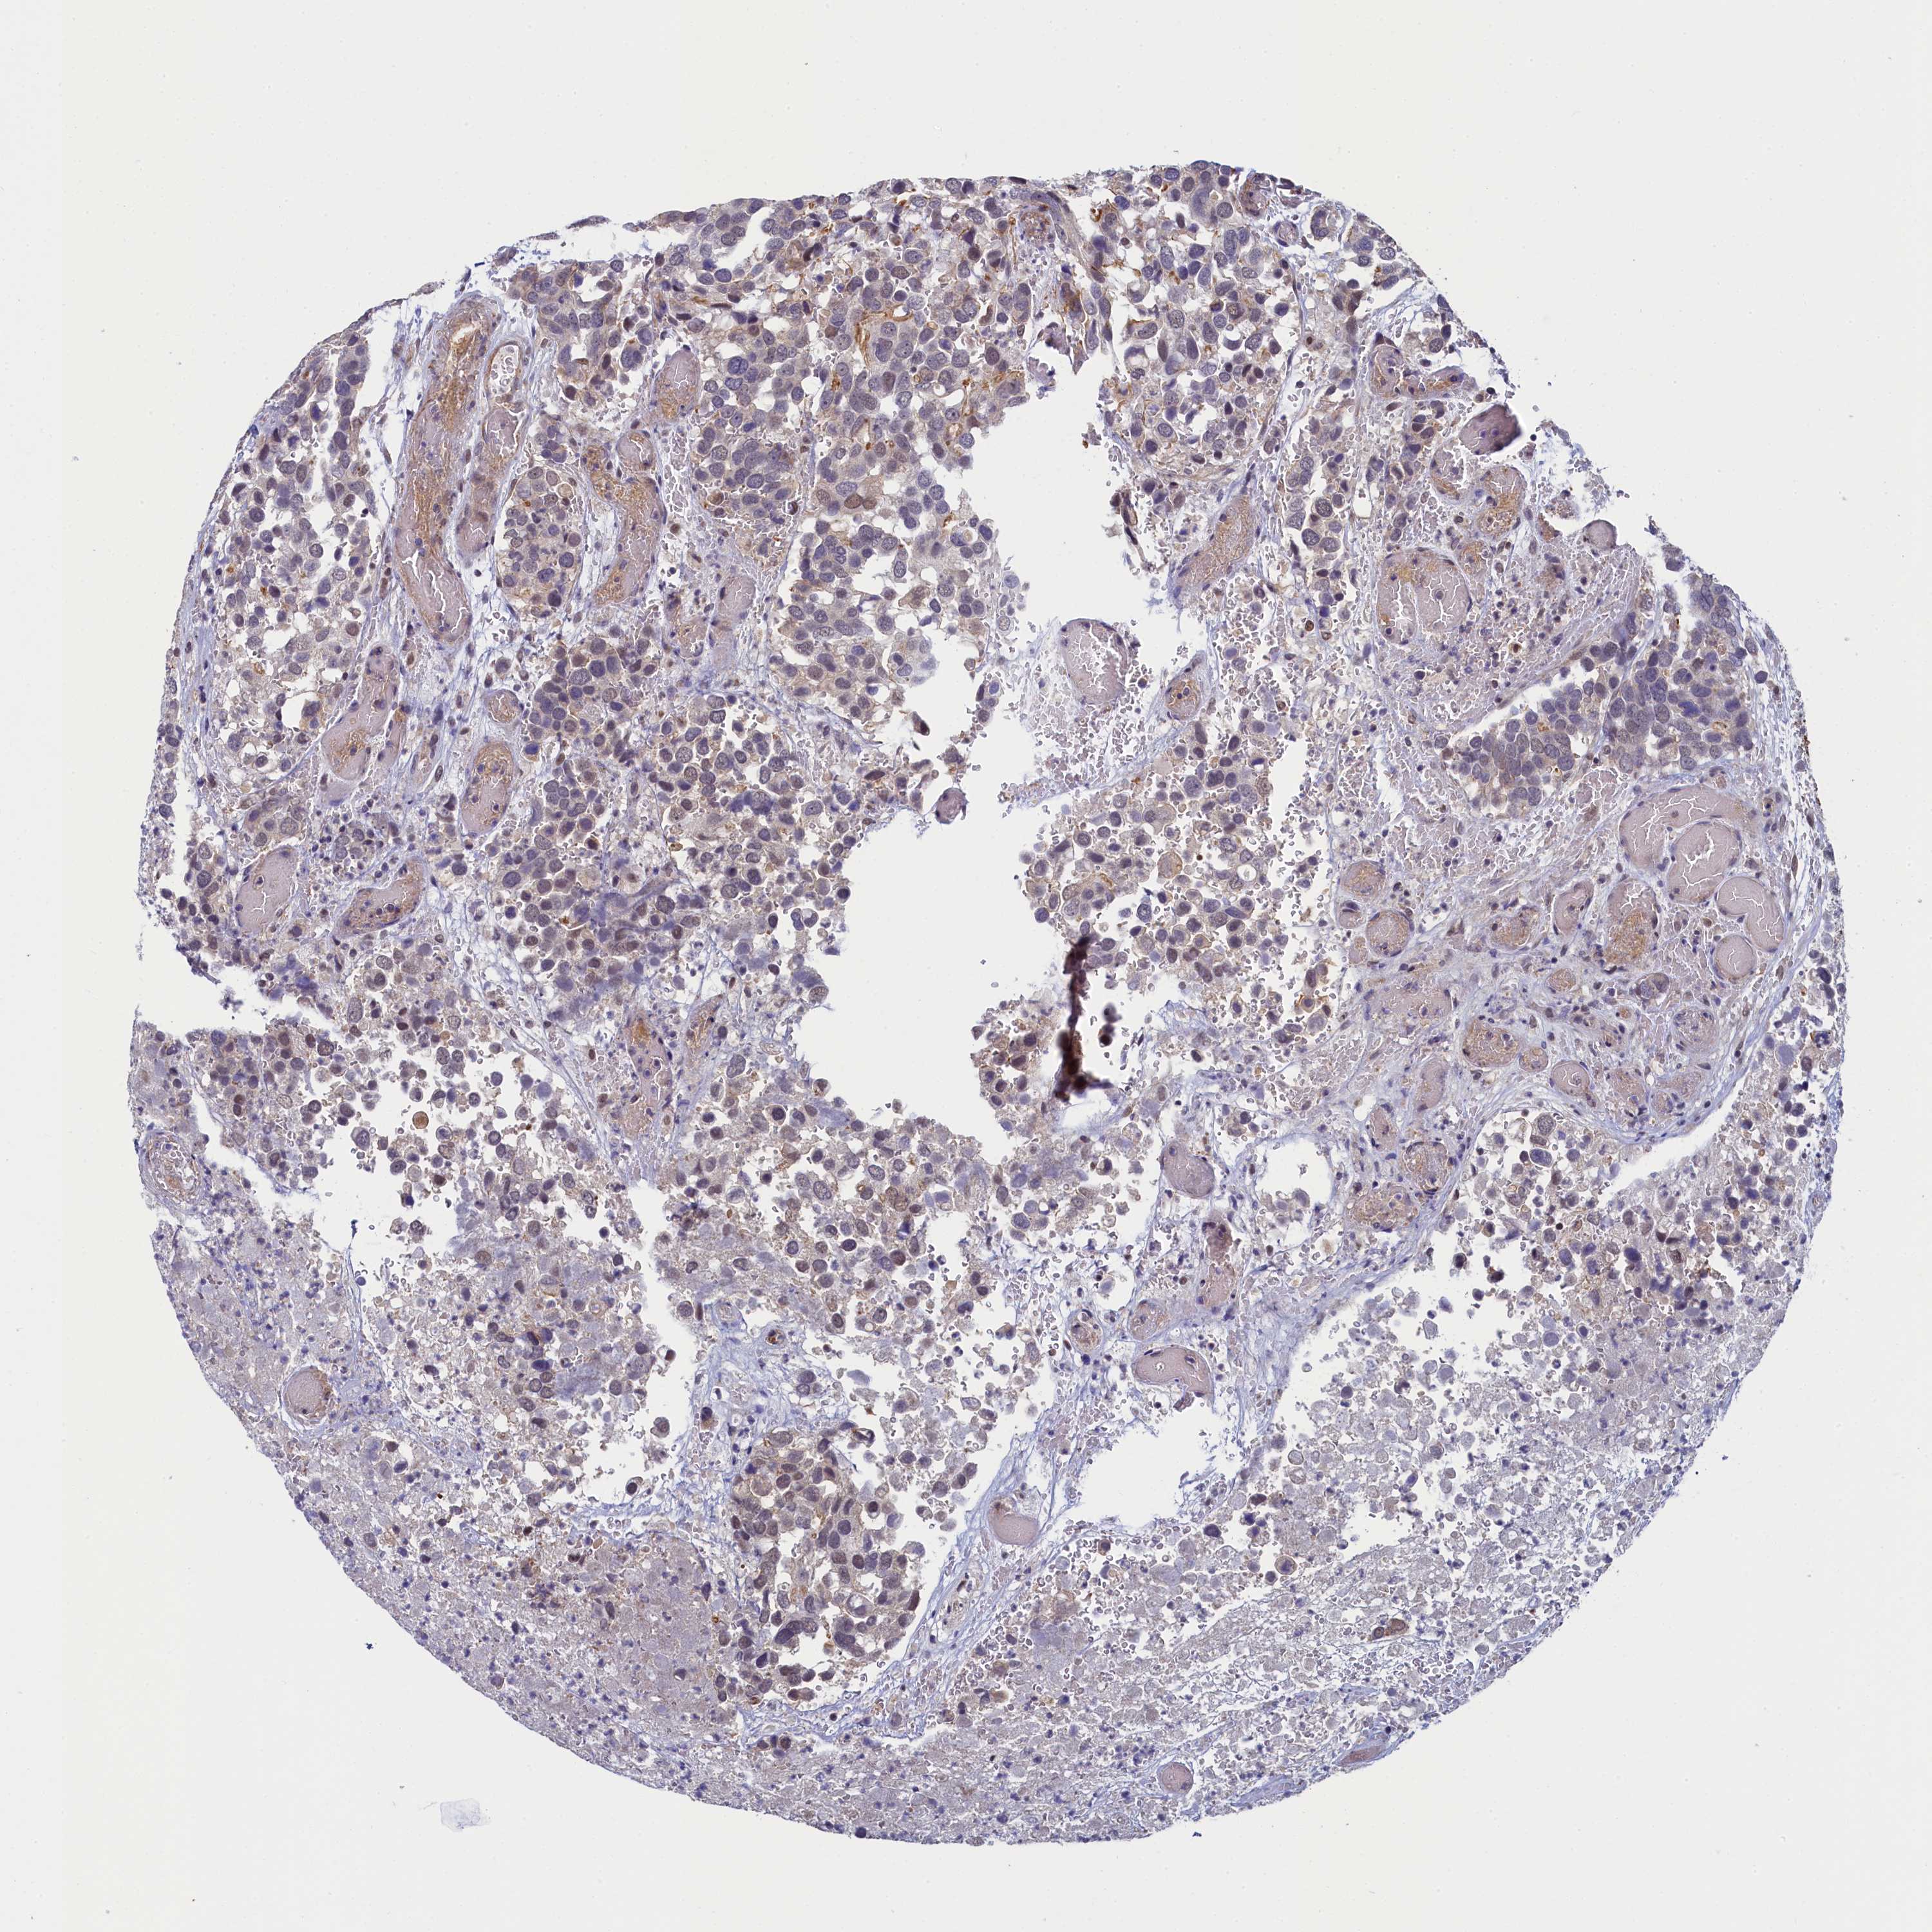

CANCER BREAST CANCER Show tissue menu

BRCA TCGA BRCA VALIDATION PROTEIN EXPRESSION

ANTIBODIES

AND

VALIDATION